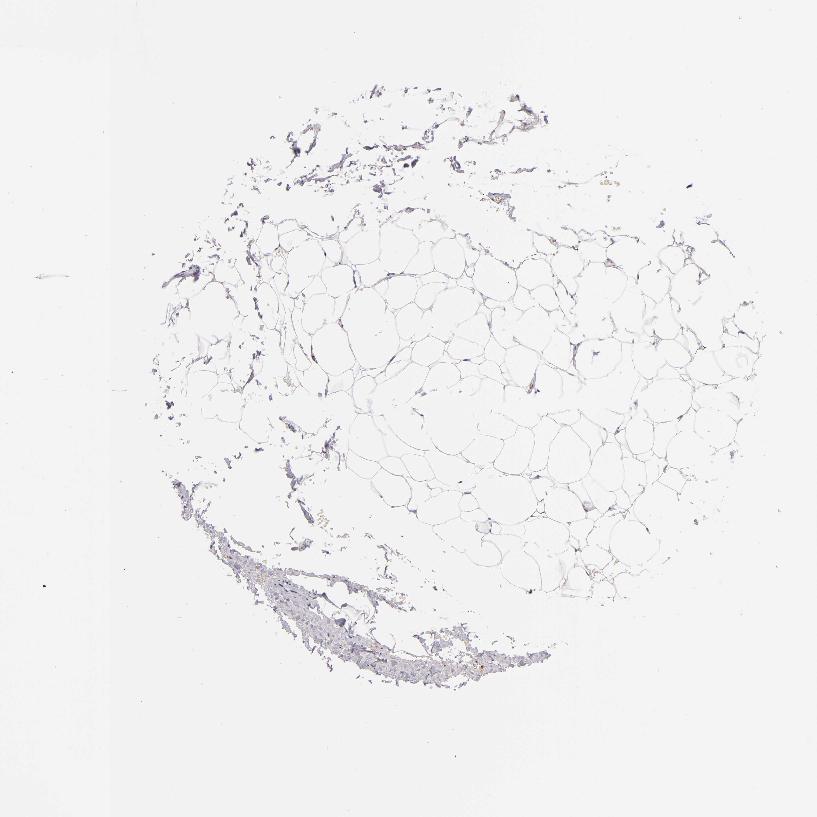

SOFT TISSUE 2 - Antibody stainingi

Antibody staining in the annotated cell types in the current human tissue is reported as not detected, low, medium, or high, based on conventional immunohistochemistry profiling in selected tissues. This score is based on the combination of the staining intensity and fraction of stained cells.

Each image is clickable and will lead to virtual microscopy that enables deeper exploration of all samples and also displays staining intensity scores, fraction scores and subcellular localization as well as patient and tissue information for each sample.

Antibody HPA013316Antibody CAB002496

Fibroblasts Not detectedNot detected

Peripheral nerve Medium-